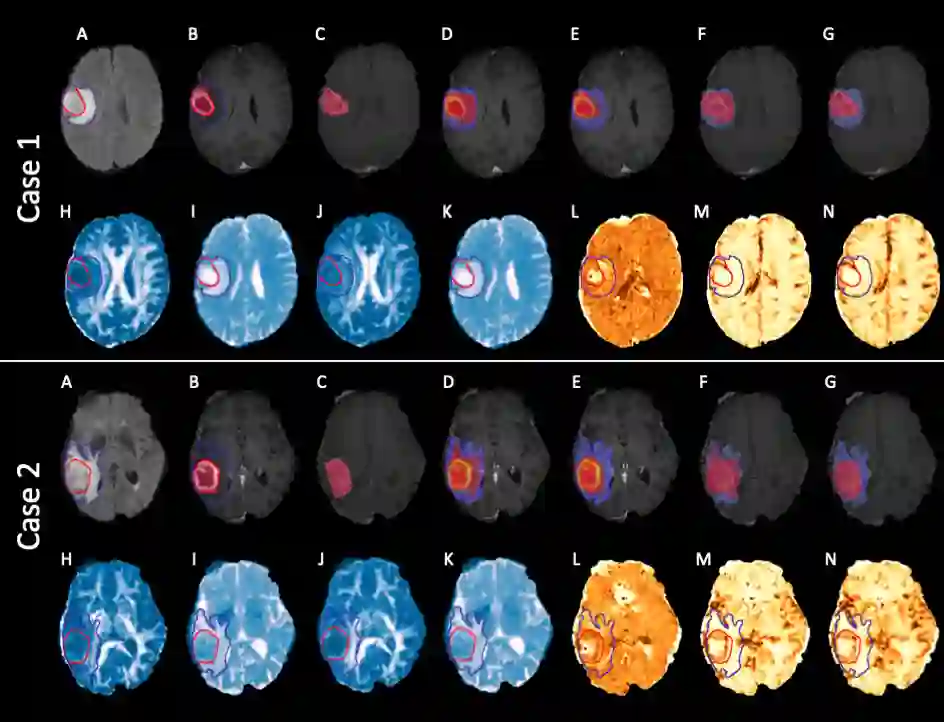

We present an Expectation-Maximization (EM) Regularized Deep Learning (EMReDL) model for the weakly supervised tumor segmentation. The proposed framework was tailored to glioblastoma, a type of malignant tumor characterized by its diffuse infiltration into the surrounding brain tissue, which poses significant challenge to treatment target and tumor burden estimation based on conventional structural MRI. Although physiological MRI can provide more specific information regarding tumor infiltration, the relatively low resolution hinders a precise full annotation. This has motivated us to develop a weakly supervised deep learning solution that exploits the partial labelled tumor regions. EMReDL contains two components: a physiological prior prediction model and EM-regularized segmentation model. The physiological prior prediction model exploits the physiological MRI by training a classifier to generate a physiological prior map. This map was passed to the segmentation model for regularization using the EM algorithm. We evaluated the model on a glioblastoma dataset with the available pre-operative multiparametric MRI and recurrence MRI. EMReDL was shown to effectively segment the infiltrated tumor from the partially labelled region of potential infiltration. The segmented core and infiltrated tumor showed high consistency with the tumor burden labelled by experts. The performance comparison showed that EMReDL achieved higher accuracy than published state-of-the-art models. On MR spectroscopy, the segmented region showed more aggressive features than other partial labelled region. The proposed model can be generalized to other segmentation tasks with partial labels, with the CNN architecture flexible in the framework.